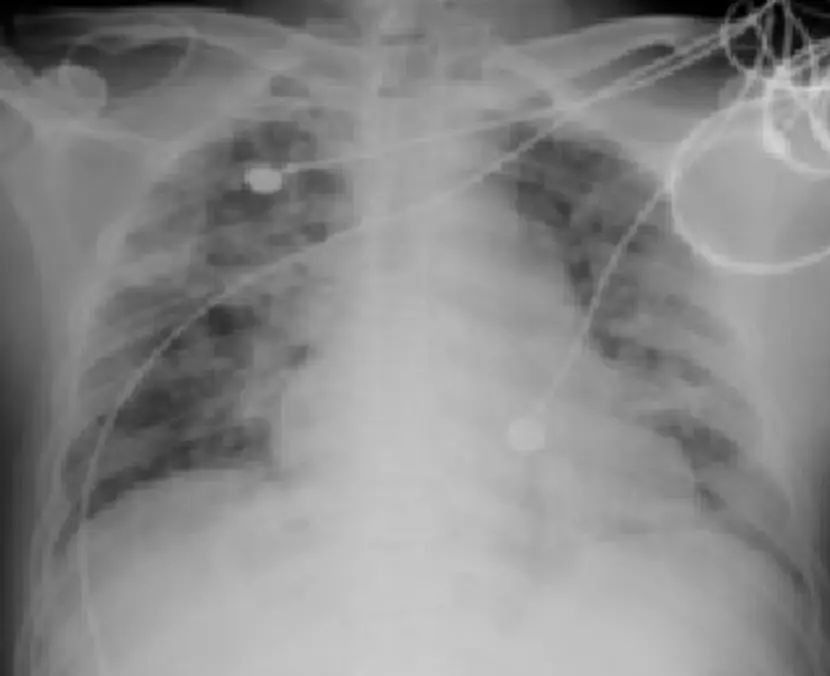

某50歲台電員工於颱風後曾至水災地區處理倒塌電線桿,約10天後出現高燒、頭痛、肌肉痠痛、咳嗽帶血、呼吸急促,住院檢查後發現:結膜下出血(如圖一)、黃疸、腎功能失常、低血鉀等。胸部X光(如圖二)請問下列敘述何者為正確?(1)此病為以動物為宿主之寄生蟲所引起;(2)必須等待病原體之血液培養結果為陽姓,方能確定診斷與開始治療;(3)發病十天後體內已產生抗體,但尿液中仍可能有病原體之存在;(4)此病即Weil's disease,有高死亡率之危險;(5)此病靠臨床診斷,須立即給予抗生素治療。 圖片描述 圖片描述

Severe icteric leptospirosis (Weil’s disease) 的 biphasic illness:初期為 leptospiremia 階段(約發病前至第7–10天),之後進入免疫階段,體內產生抗體但Leptospira 持續自尿液排出,且典型併發有肝腎功能障礙、肺出血及結膜充血/出血。

2. 胸部X光:雙側肺野散在不均勻的實質浸潤,部分區域呈磨玻璃密度,提示肺部出血或急性呼吸窘迫症候群(ARDS),與 Weil’s disease 中可見的重度肺出血相符。